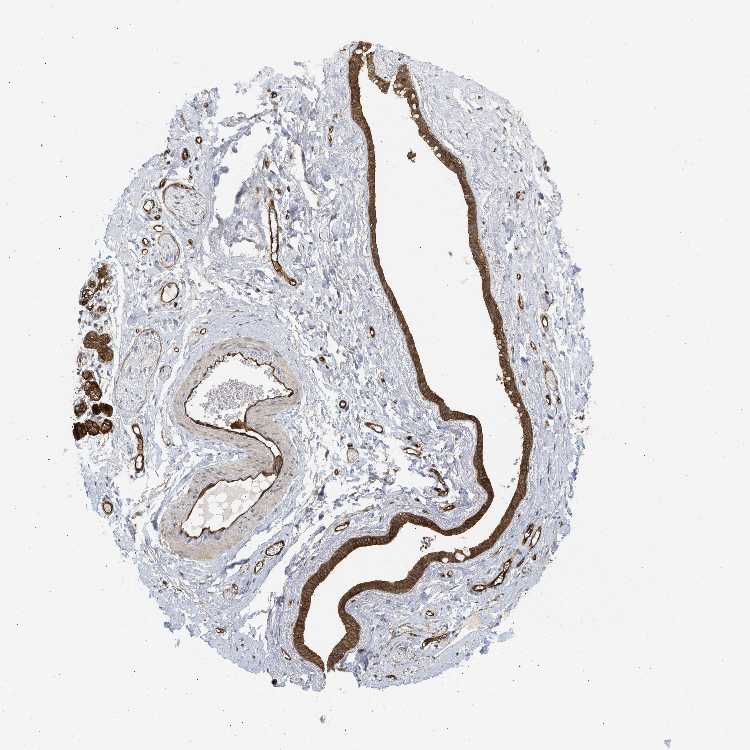

SOFT TISSUE 1 - Antibody stainingi

Antibody staining in the annotated cell types in the current human tissue is reported as not detected, low, medium, or high, based on conventional immunohistochemistry profiling in selected tissues. This score is based on the combination of the staining intensity and fraction of stained cells.

Each image is clickable and will lead to virtual microscopy that enables deeper exploration of all samples and also displays staining intensity scores, fraction scores and subcellular localization as well as patient and tissue information for each sample.

Antibody HPA017959Antibody HPA030549

Chondrocytes -Medium

Fibroblasts Not detectedHigh

Peripheral nerve Not detected-